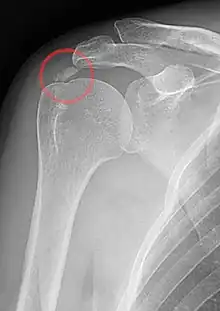

| A plain X ray of the shoulder showing calcific tendinitis | |

Calcific tendinitis is typically diagnosed by physical examination and X-ray imaging.[1] During the formative phase, X-ray images typically reveal calcium deposits with uniform density and a clear margin.[1] In the more painful resorptive phase, deposits instead appear cloudy and with unclear margins.[1] By arthroscopy, formative stage deposits appear crystalline and chalk-like, while resorptive stage deposits appear smooth resembling toothpaste.[1] Ultrasound is also used to locate and assess calcium deposits. In the formative stage, deposits are hyperechoic and arc-shaped; in the resorptive stage deposits are less echogenic and appear fragmented.[1][3]